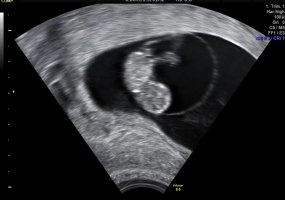

Her er bamsemumset vårt, med bankende hjerte

For en følelse! For en glede! Lille venn har navlesnoren i morkaken nå så den mest kritiske fasen var over sa jordmor. Alt så helt supert ut

Hun målte lille til 2,13 cm og nøyaktig 8+5 i dag, som er nøyaktig samme dagen jeg har